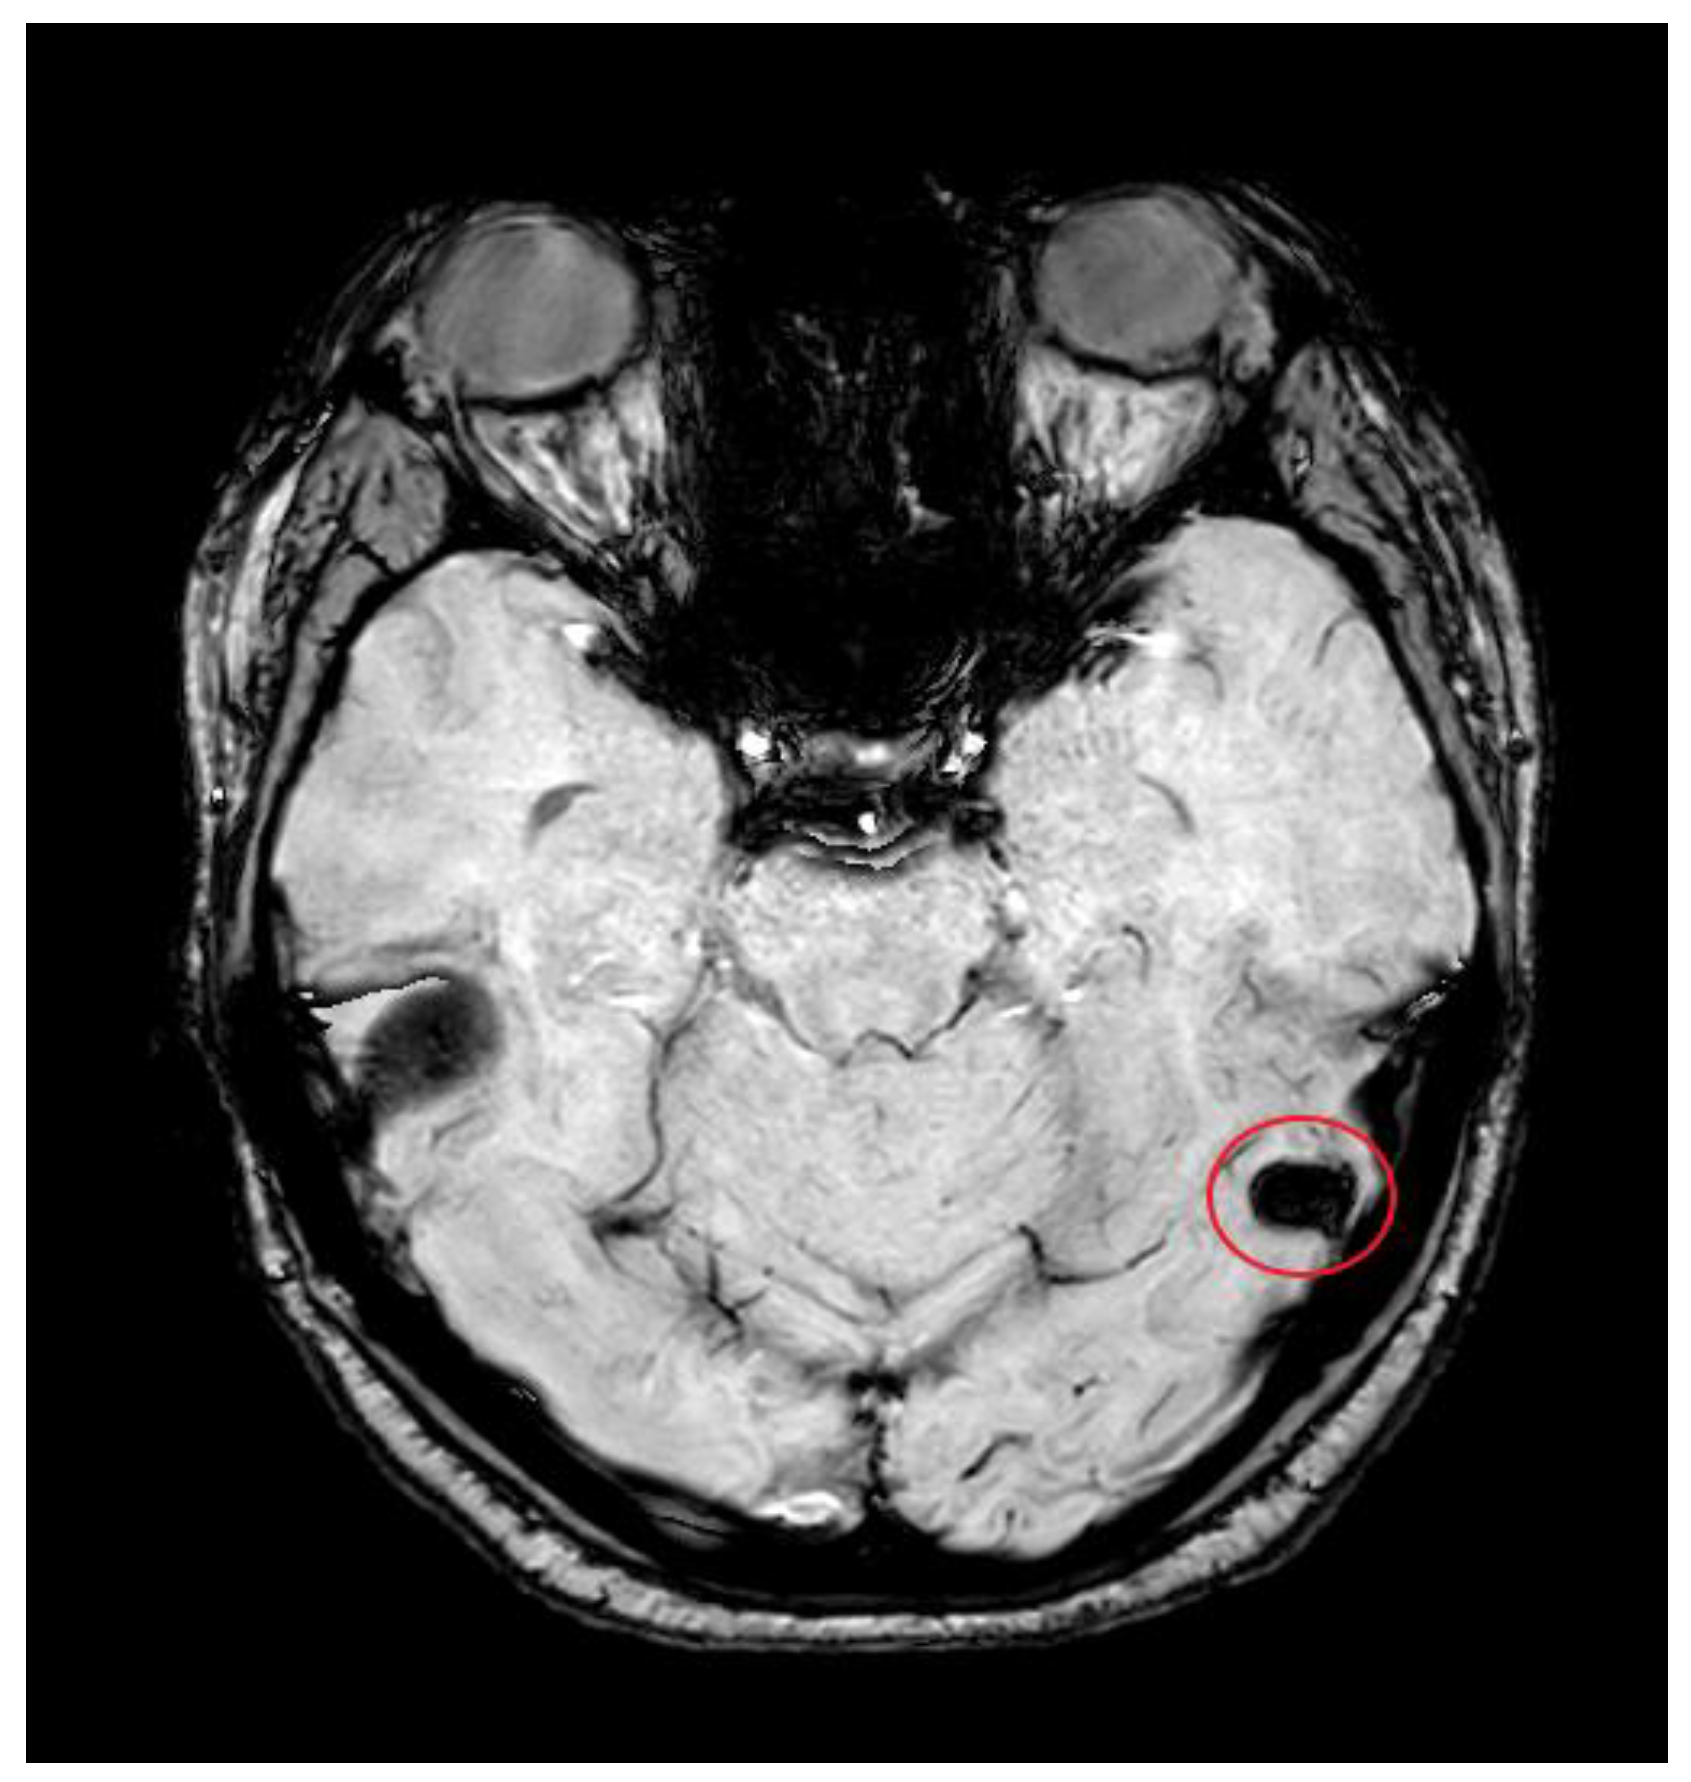

3.2. Imaging Role